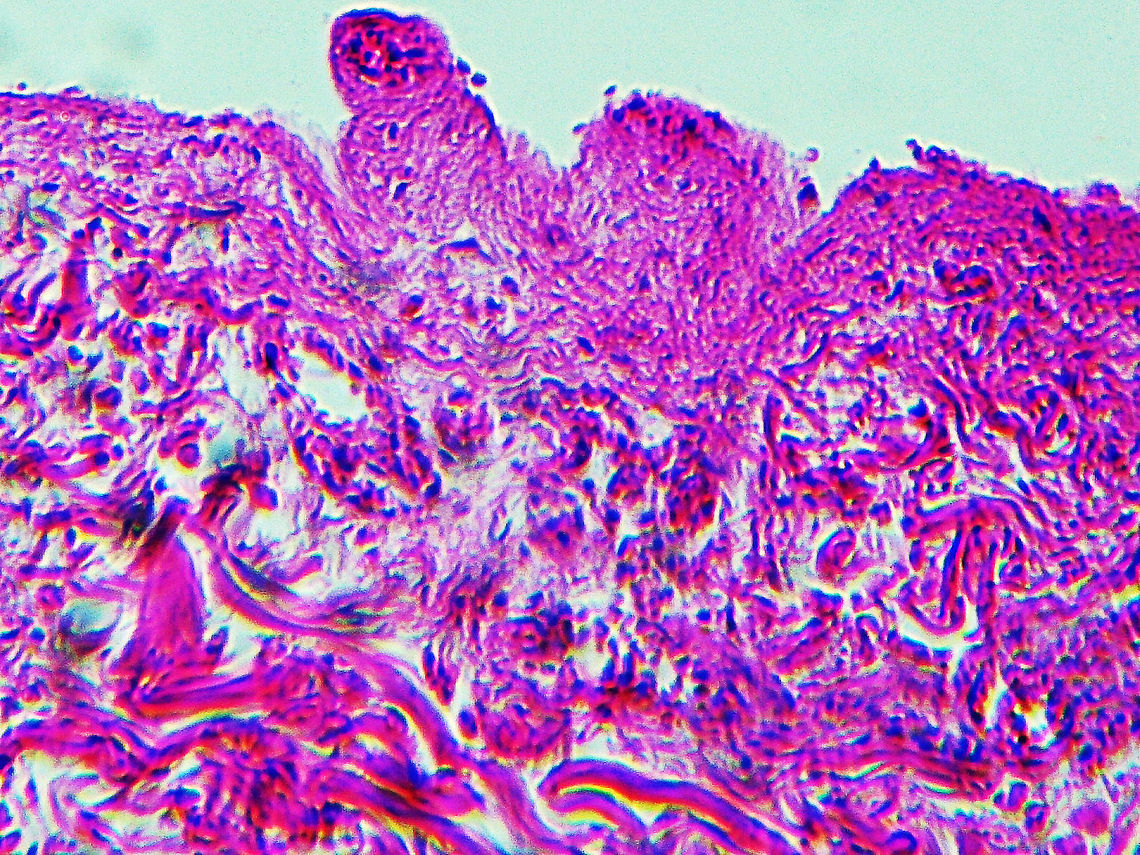

This slide is a skin biopsy from a person infected with Rickettsia rickettsii (the causative agent of Rocky Mountain Spotted Fever). It shows necrosis, vasculitis, and inflammation.

RMSF is a serious, life-threatening tick-borne disease. It's often misdiagnosed. A classic RMSF symptom is a rash, which occurs in about 90% of patients. The disease was first identified in the Rocky Mountains, but can also be found in parts of Canada, Mexico, as well as South and Central America.